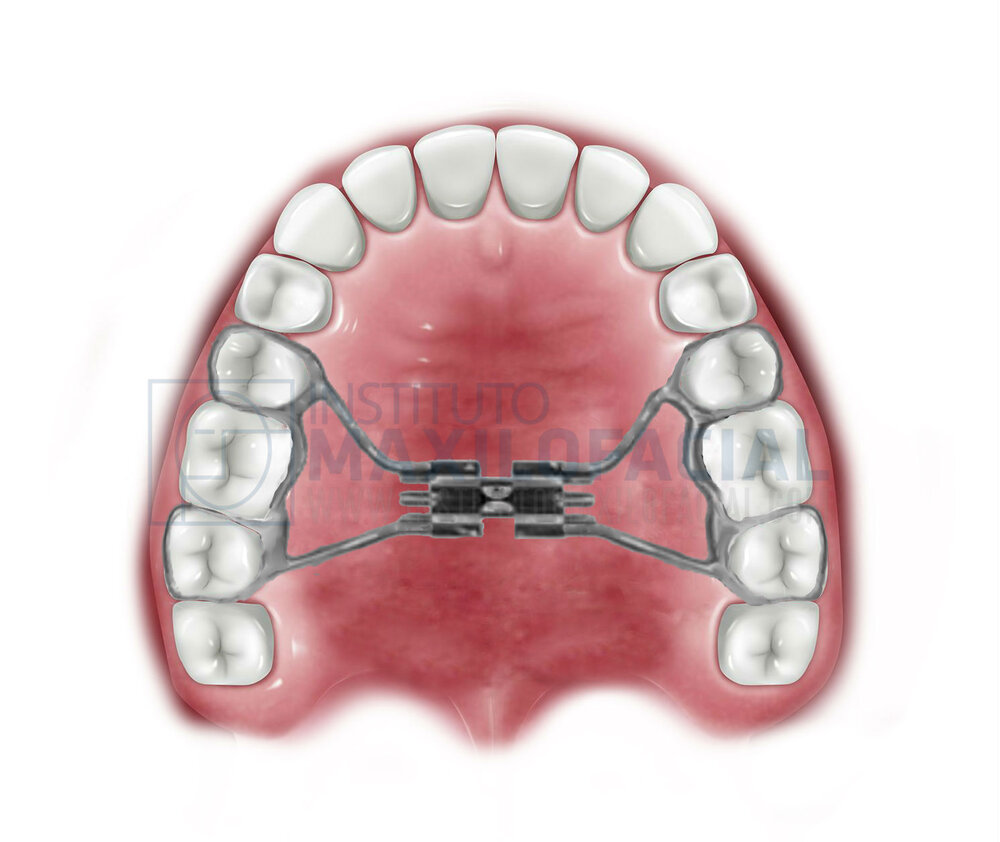

This is MSE:

Expands the width of maxilla, mouth, nasal base, and zygomatics expansion. You would need corticopuncture done so you can expand with MSDO at the same rate.

Expands the width of maxilla, mouth, nasal base, and zygomatics expansion. You would need corticopuncture done so you can expand with MSDO at the same rate.

MSE Results (Cheekbones width, maxilla).

10mm of MSE equals =

8.4 mm - cheekbones width (0.84mm gain for every milimeter of MSE expansion)

1.2 mm - Maxilla forward growth (upper and lower)

10mm of MSE equals =

8.4 mm - cheekbones width (0.84mm gain for every milimeter of MSE expansion)

1.2 mm - Maxilla forward growth (upper and lower)